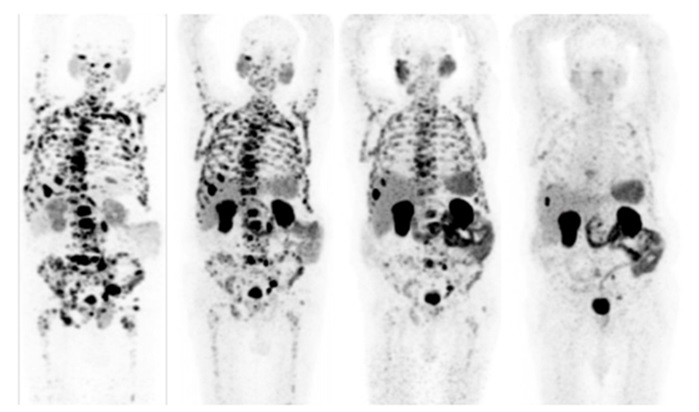

Với sự phát triển của y học hạt nhân, việc chẩn đoán và theo dõi kết quả điều trị ung thư bằng kỹ thuật chụp cắt lớp phát xạ positron (PET) đã có rất nhiều tiến bộ trong việc xác định vị trí khối u và vùng xâm lấn cũng như vị trí di căn (nếu có). Dựa trên nguyên tắc của kỹ thuật PET, các nhà khoa học đã phát triển công nghệ Theranostic có khả năng xác định vị trí khối u và vùng xâm lấn, đồng thời tiêu diệt ngay các tế bào ung thư trong khối u và vùng xâm lấn mà không làm ảnh hưởng đến các tế bào khỏe mạnh bên cạnh. Đây được xem là công nghệ y học hạt nhân hiện đại hay y học chính xác có khả năng chữa trị ung thư cho từng cá thể khác nhau và các loại ung thư khác nhau. Bí quyết của công nghệ Theranostic là gắn 2 loại đồng vị phóng xạ (1 loại cho chẩn đoán và 1 loại cho điều trị) vào một loại chất mang là dinh dưỡng cao cấp và tiêm hỗn hợp này vào tĩnh mạch. Khi đó, các tế bào ung thụ sẽ hấp thụ loại dinh dưỡng cao cấp, còn tế bào thường thì không. Do đó khi ghi hình sẽ xác định được vị trí khối u bởi bức xạ gamma của đồng vi phóng xạ thứ nhất và loại bức xạ (alpha hoặc beta) của đồng vị thứ 2 sẽ tiêu diệt tế bào ung thư.

Tiến bộ của kỹ thuật Theranostic đối với việc điều trị bệnh nhân 82 tuổi bị ung tiền liệt tuyến (Hình ảnh từ trái qua phải: hình ảnh di căn của khối u vào trong xương và u lympho trên da, kết quả điều trị bằng kỹ thuật Theranostic các di căn mất dần cho đến hình cuối cùng là hoàn toàn sạch các di căn).